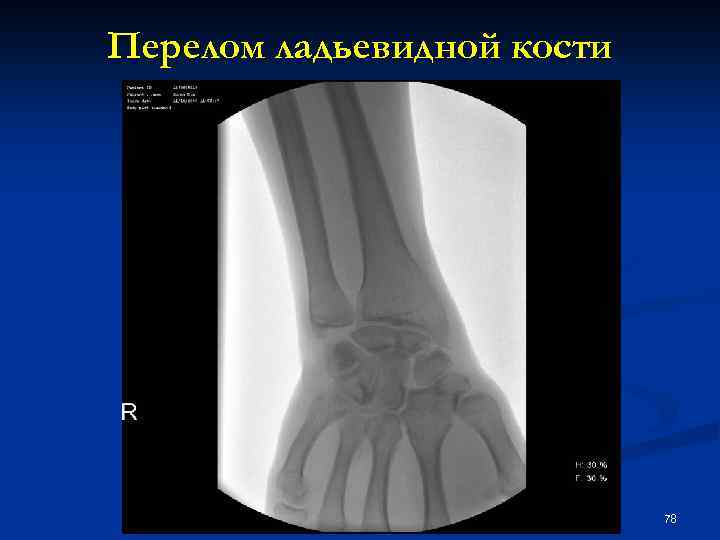

Перелом ладьевидной кости 78